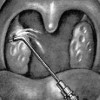

Вскрытие кисты миндалины

Вскрытие кисты миндалины – операция, включающая в себя разрез стенки кисты и удаление ее содержимого. Осуществляется при неэффективности консервативной терапии, постоянном ощущении першения и инородного тела в горле, изменении голоса и болях при глотании, обусловленных кистой миндалины. Всего в Перми найдено 9 клиник, где выполняют вскрытие кисты миндалины.